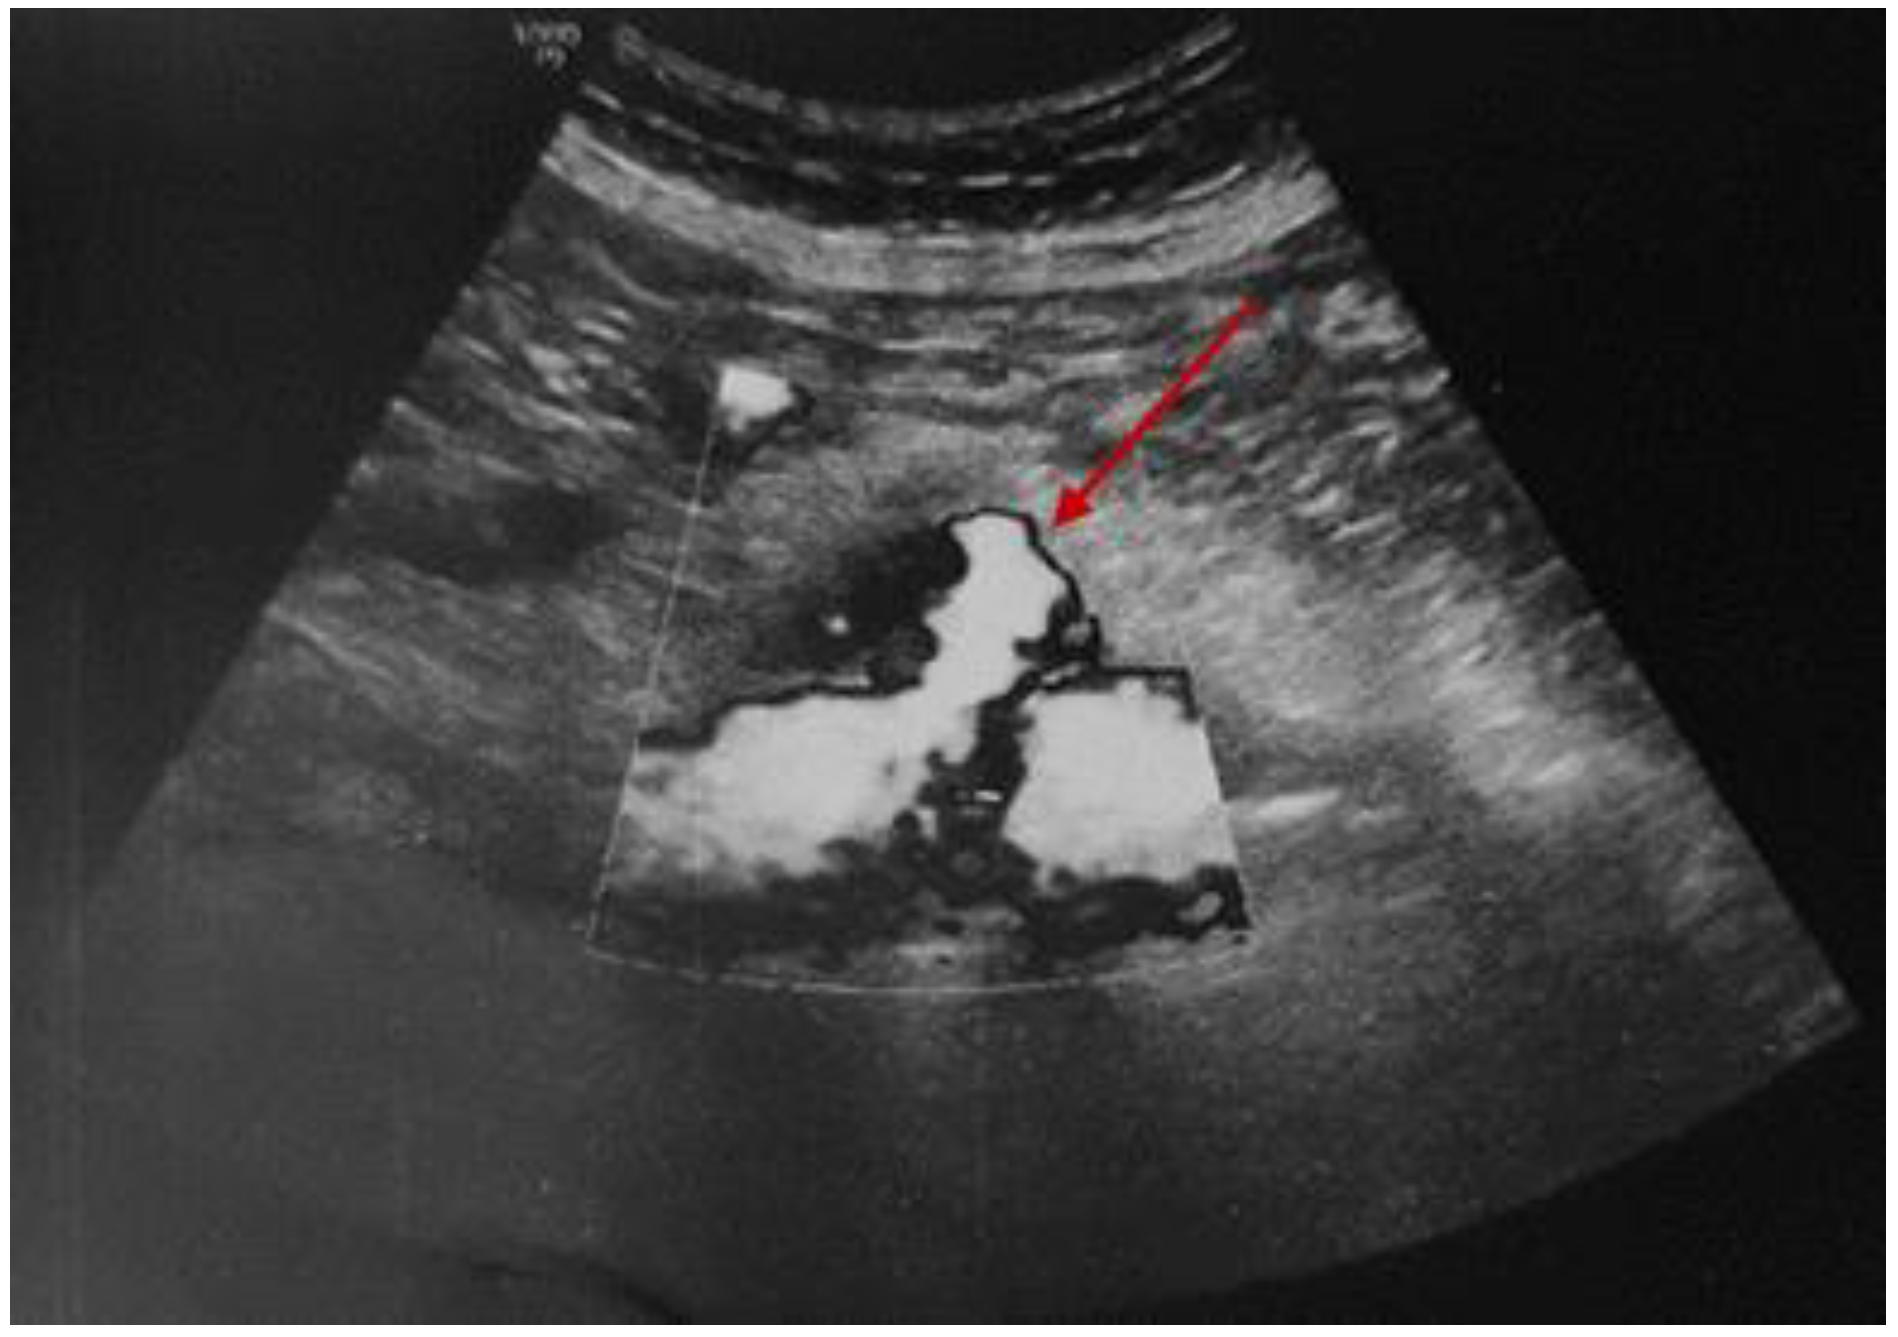

3.2.1. A Fine Index of Clinical Suspicion: Low Back Pain

3.2.2. Additional Imaging Assessments